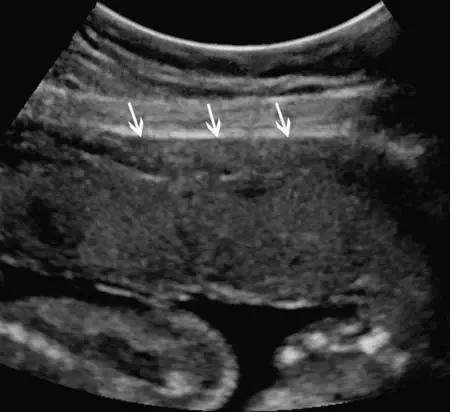

中孕时,胎盘逐渐成熟变大,表现为更加均质的高回声(图 2),其内可有边界欠清的低回声区,为胎盘湖。晚孕时,多普勒超声可显示胎盘内的丰富血流。

图 2 孕 24 周时的正常胎盘横切面,显示胎盘的回声、厚度及其后方的低回声肌壁(箭头)